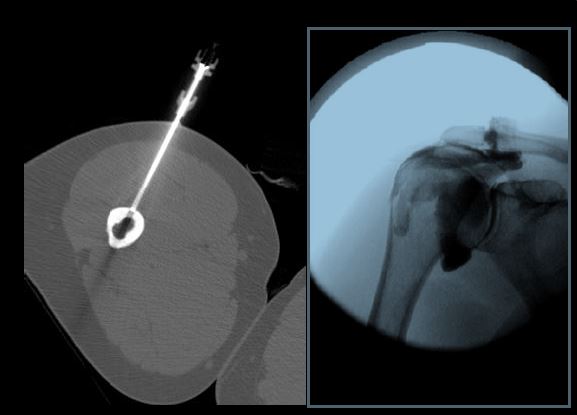

• To train fellows to become skilled in the selection, performance and interpretation of image guided intervention including fluoroscopy, CT and ultrasound guided musculoskeletal therapeutic procedures including fenestrations and steroid injections.

A wide range of diagnostic services including radiography, US, CT, MRI, and arthrography are complemented by an active MSK interventional service providing diagnostic arthrography, joint injections, and bone and soft tissue biopsies.

University Campus is located on Lake Avenue North and is home to the UMass Chan Medical School and its research facilities. UMMMC’s trauma center and ambulatory care center (ACC) are located on this campus providing a large volume of orthopedic cases. University Campus is the primary site of all MSK ultrasound examinations and all image guided MSK interventional cases are performed at this campus.